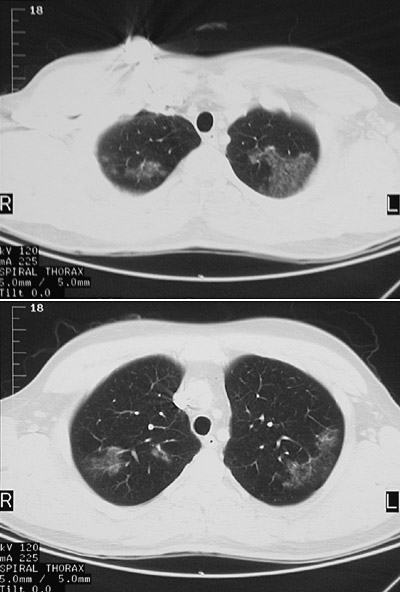

| These CT scan views in "lung window" reveal upper lobe patchy infiltrates in a patient who underwent bronchoalveolar lavage and was found to have Pneumocystis carinii (jirovecii) organisms present. This patient had presented with a three day history of fever, non-productive cough, and increasing dyspnea. |